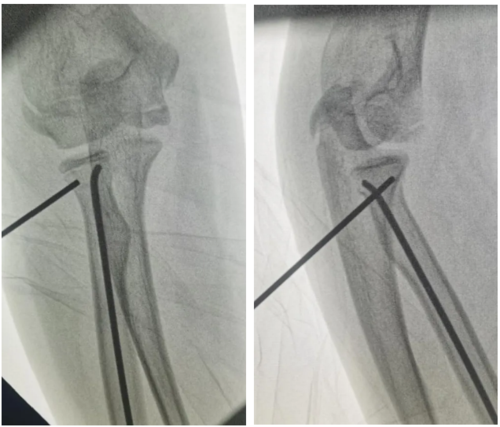

捕获.PNG

术前X片见桡骨颈成角移位

手术当日,向飞帆博士、何兴远副主任医师与张维孟主治医师同台协作,在C臂机实时影像引导下,术者精准定位骨折断端,仅通过一个“针眼”大小的入路置入克氏针,轻柔撬拨移位骨块,实现骨折“解剖复位”(断端恢复至原有解剖位置);随后在桡骨远端作 1.5cm 微小切口,顺利置入弹性髓内钉完成固定。整个手术过程创伤极小,术中出血量不足 5ml。

捕获2.PNG

▲克氏针微创撬拨复位